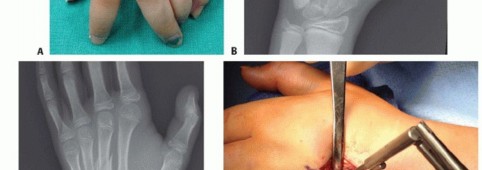

Absolute indications for operative intervention are non-negotiable scenarios where conservative management is guaranteed to yield an unacceptable functional outcome. Chief among these is rotational malalignment. As previously established, any degree of clinical scissoring during digital flexion is an absolute mandate for surgical derotation and fixation. Open fractures, particularly those heavily contaminated or resulting from human or animal bites ("fight bites"), require urgent surgical débridement, irrigation, and concurrent stabilization to mitigate the catastrophic risk of deep space infection and osteomyelitis. Furthermore, highly unstable fractures, such as those involving the border metacarpals (index and small finger) which lack the tethering support of adjacent intact rays on both sides, typically demand surgical fixation to prevent progressive collapse.

Clinical Evaluation and Advanced Imaging

A rigorous, systematic clinical assessment is the first step in preoperative planning. Inspection must evaluate the hand at rest, noting the natural digital cascade, and through a full active arc of motion. The surgeon must critically assess for any deviation of the nail beds during flexion, the hallmark of rotational malalignment. Palpation should trace the dorsal contour of the metacarpals to identify fracture step-offs, while simultaneous volar palpation assesses for symptomatic metacarpal head prominence. The surgeon must maintain a high index of suspicion for associated injuries, meticulously examining the skin for subtle puncture wounds over the MCP joints that signify a human tooth strike, and evaluating the CMC joints for subtle subluxations that frequently accompany basilar fractures.

Open Reduction and Internal Fixation (ORIF) Approaches

When closed reduction fails, or for complex, comminuted, or multiple metacarpal fractures, Open Reduction and Internal Fixation (ORIF) is mandated. A dorsal longitudinal or slightly gently curved incision is made centered over the fractured metacarpal. Careful subcutaneous dissection is performed to identify and meticulously retract the dorsal sensory nerve branches using vessel loops. The extensor apparatus is exposed. Depending on the fracture location, the extensor tendon can be retracted laterally, or the extensor mechanism can be split longitudinally (e.g., splitting the EDC tendon) to access the dorsal periosteum.

Periosteal elevation must be judicious and strictly limited to the footprint required for plate application. Circumferential stripping of the periosteum is a catastrophic error that devascularizes the bone fragments and invites nonunion. The fracture site is gently debrided of hematoma and interposed soft tissue. Anatomical reduction is achieved using specialized reduction forceps, taking immense care to avoid crushing fragile cortical edges. Provisional fixation is maintained with fine (0.035-inch or 0.045-inch) K-wires.